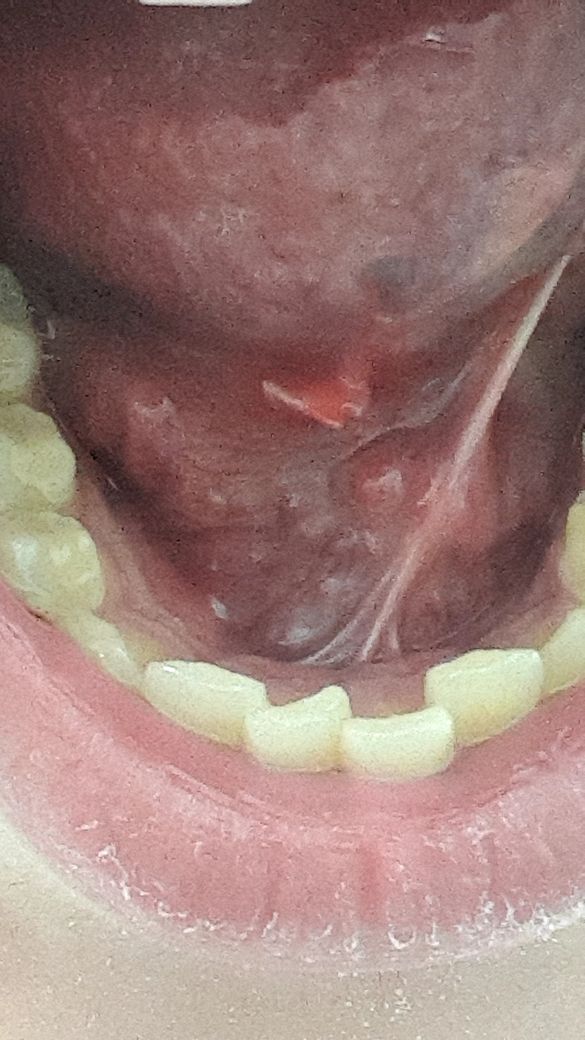

혀가 며칠전부터 많이 아프고 보니까 혀 아래에 뭐가 났더라고요.. 제가 평소에 보던 구내염 모양도 아니라서 이게 대체 뭔가 싶은데..이게 뭘까요..?

혀 아래의 점액낭종이 발생한 것으로 보입니다.

현재 사진상으로 명확히 알기는 어렵지만 섬유종이나 점액종을 감별하는 것이 필요해 보입니다. 내원하시어 진료를 받아보시기 바랍니다.